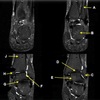

120

MEDIAL RETINACULYM

What is letter M?

122

LATERAL PATELLAR RENTINACULUM

What is letter O?

124

ARTICULAR CARTILAGE

What is letter A?

126

MEDIAL COLLATERAL LIGAMENT

What is letter C?

128

TIBIAL PLATEAU

What is letter E?

130

LATERAL COLLATERAL LIGAMENT

132

FEMUR

134

TIBIA

136

POSTERIOR HORN OF LATERAL MENISCUS

138

PATELLA

140

142

DISTAL FEMUR